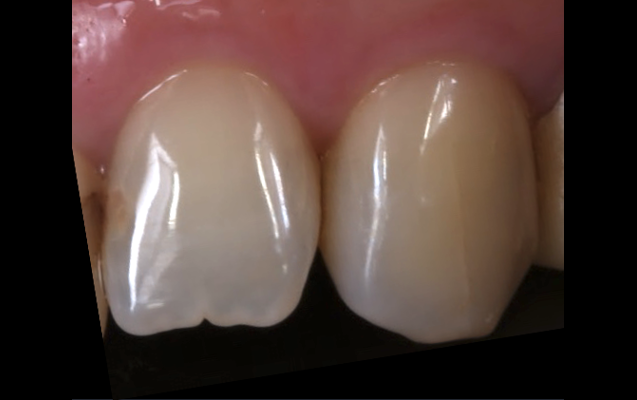

「歯冠長延長術(クラウンレングスニング)」は、歯肉を切開し、歯を支える骨(歯槽骨)を削ることで、治療が必要な部分を露出させる方法です。虫歯等が進行し、歯ぐきが覆いかぶさった状態になってしまっている場合に、歯ぐきを少し下げ治療を施すものです。

歯ぐきを上に露出させることで、精密な印象採得や、細菌感染の起こしにくい環境を作り、結果として長持ちさせる治療が可能となります。

(実際の症例)